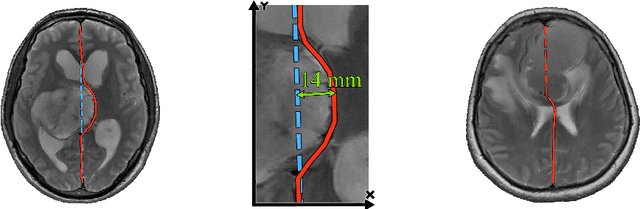

Abstract:Midline shift (MLS) is a well-established factor used for outcome prediction in traumatic brain injury, stroke and brain tumors. The importance of automatic estimation of MLS was recently highlighted by ACR Data Science Institute. In this paper we introduce a novel deep learning based approach for the problem of MLS detection, which exploits task-specific structural knowledge. We evaluate our method on a large dataset containing heterogeneous images with significant MLS and show that its mean error approaches the inter-expert variability. Finally, we show the robustness of our approach by validating it on an external dataset, acquired during routine clinical practice.